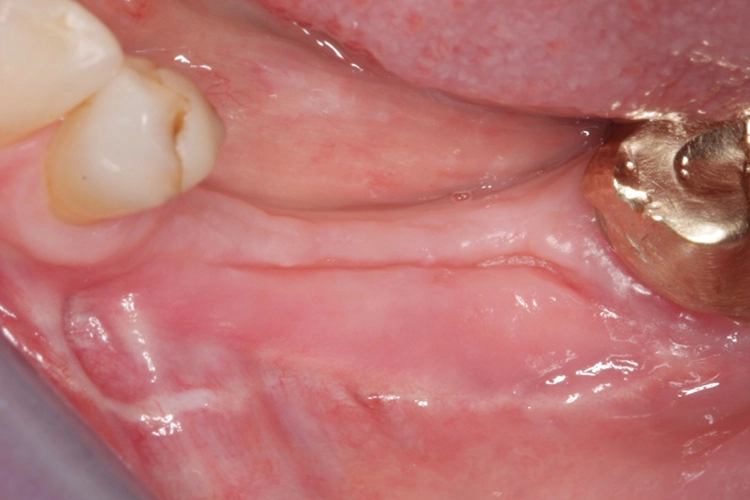

Der Prämolar 35 wies einen hohen Lockerungsgrad und Knochenabbau auf und musste daher extrahiert werden (Abb. 2). Nach einer Ausheilungsphase von sechs Wochen erfolgte die Rekonstruktion des verlorengegangenen Knochens (Abb. 3 und 4). Es erfolgte die Knochenentnahme retromolar und die Schalen wurden in der Folge mit Hilfe des sog. Safescrapers (Firma Meta) weiter ausgedünnt. Nun erfolgte die Rekonstruktion des Knochendefekts, wobei die zuvor entnommenen Knochenschalen (Split Bone Technik nach Prof. Khoury) bukkal auf Distanz gesetzt und mit kleinen Osteosyntheseschrauben fixiert wurden.

Die Wiedereröffnung des Operationsgebietes erfolgte nach vier Monaten. Länger sollte nicht mit dem Re-entry gewartet werden. Es zeigte sich, dass nur wenig keratinisierte Schleimhaut am Tag der Freilegungsoperation vorhanden war. Daher wurde sich für die sog. Kazanjian Vestibulumplastik entschieden, mit der wieder ein Vestibulum und damit auch fixierte Schleimhaut im periimplantären Bereich hergestellt werden kann (Abb. 10 und 11).